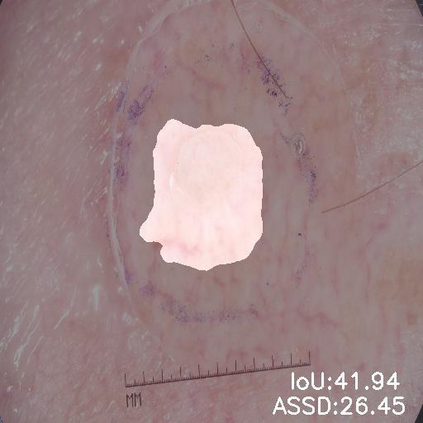

Skin lesion segmentation from dermoscopy images is of great significance in the quantitative analysis of skin cancers, which is yet challenging even for dermatologists due to the inherent issues, i.e., considerable size, shape and color variation, and ambiguous boundaries. Recent vision transformers have shown promising performance in handling the variation through global context modeling. Still, they have not thoroughly solved the problem of ambiguous boundaries as they ignore the complementary usage of the boundary knowledge and global contexts. In this paper, we propose a novel cross-scale boundary-aware transformer, \textbf{XBound-Former}, to simultaneously address the variation and boundary problems of skin lesion segmentation. XBound-Former is a purely attention-based network and catches boundary knowledge via three specially designed learners. We evaluate the model on two skin lesion datasets, ISIC-2016\&PH$^2$ and ISIC-2018, where our model consistently outperforms other convolution- and transformer-based models, especially on the boundary-wise metrics. We extensively verify the generalization ability of polyp lesion segmentation that has similar characteristics, and our model can also yield significant improvement compared to the latest models.